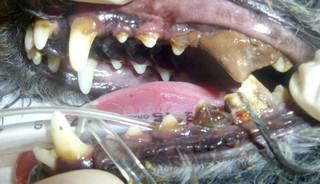

重度に付着した歯石をスケーリングすると・・・

歯槽骨が破壊されて奥歯の歯根が露出してしまっています